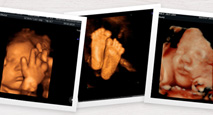

Ecografías 4D-5D

Deja de imaginar cómo será, ¡ahora puede ver la cara de tu bebé antes de que nazca! Con las ecografías 3D/4D/5D podrás ver a tu bebé en tres dimensiones y en movimiento.